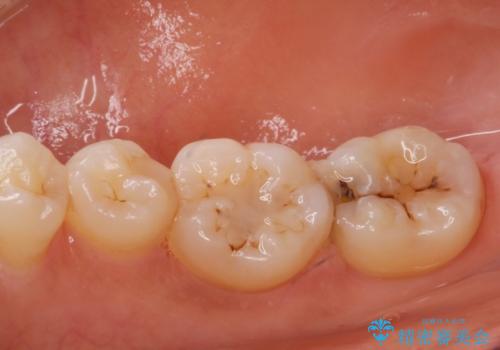

虫歯により歯が欠けていたので拡大鏡下で虫歯を除去した後、セラミックの詰め物で治療しました。

- e-maxインレー 7.7万円 費用は治療当時の料金となります

適合の良い詰め物が入りました。

セラミックスは虫歯の再発のリスクが低くなります。